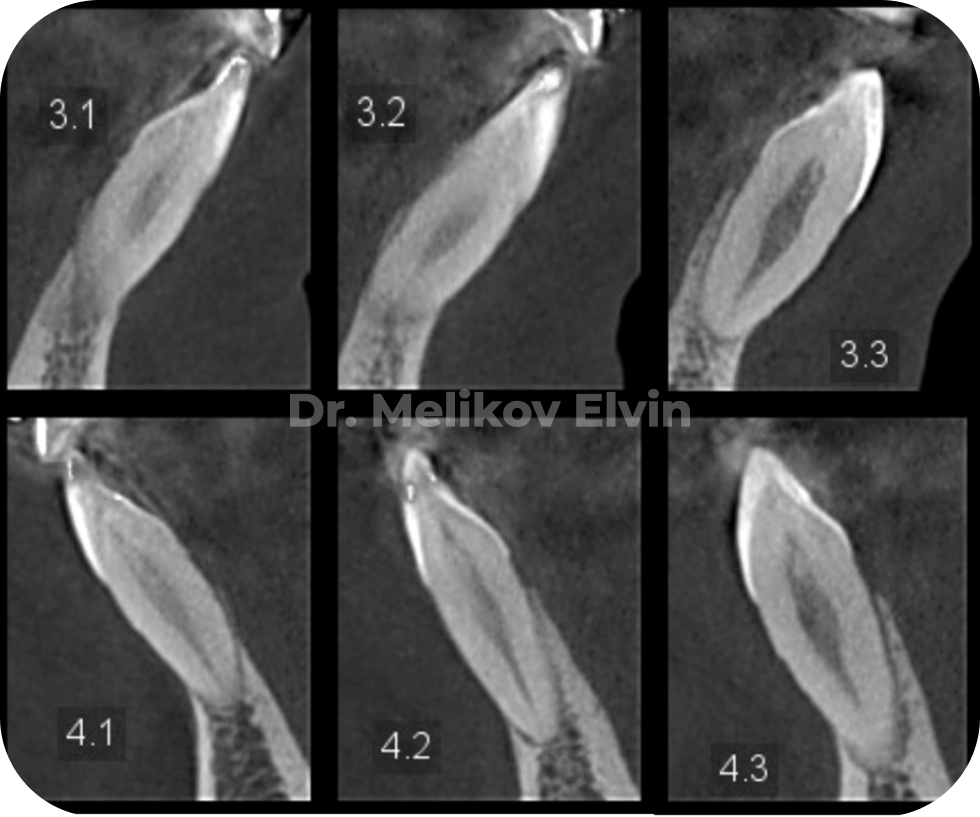

На снимках можно увидеть воссозданный объём наружной кортикальной пластинки в проекции корней зубов.

До костной пластики на нижней челюсти